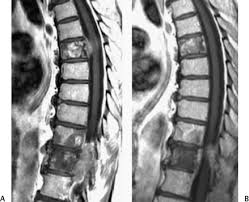

Https Onlinelibrary Wiley Com Doi Pdf 10 1002 Pros 2990250305

Https Onlinelibrary Wiley Com Doi Pdf 10 1002 Pros 2990250305 from